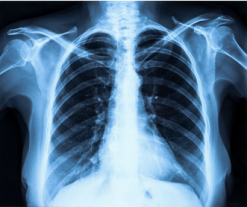

NVFlare and its predecessors have been used in several real-world studies exploring FL for healthcare scenarios. The collaborations between multinational institutions tested and validated the utility of federated learning, pushing the envelope for training robust, generalizable AI models. These initiatives included FL for breast mammography classification [32], prostate segmentation [33], pancreas segmentation [37], and most recently, chest X-ray (CXR) and electronic health record (EHR) analysis to predict the oxygen requirement for patients arriving in the emergency department with symptoms of COVID-19 [6].